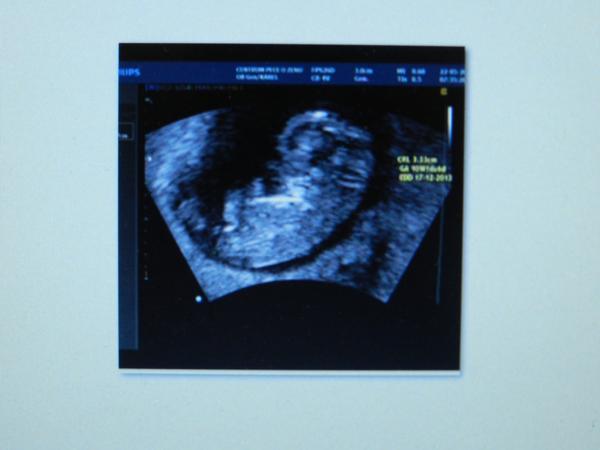

@ratatooy jéééé modrásek. krásná fotka